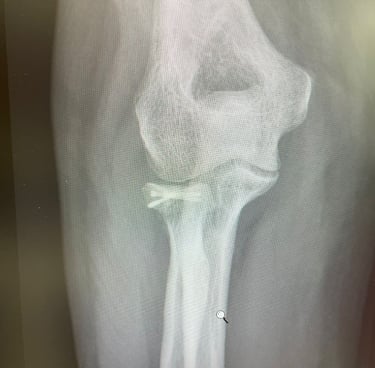

Mi occupo del trattamento traumatico sia in forma conservativa sia chirurgica. Tratto fratture, lussazioni, lesioni dei legamenti e dei tendini, con l’obiettivo di ripristinare la funzionalità articolare, ridurre il dolore e favorire un rapido ritorno alle attività quotidiane e sportive.